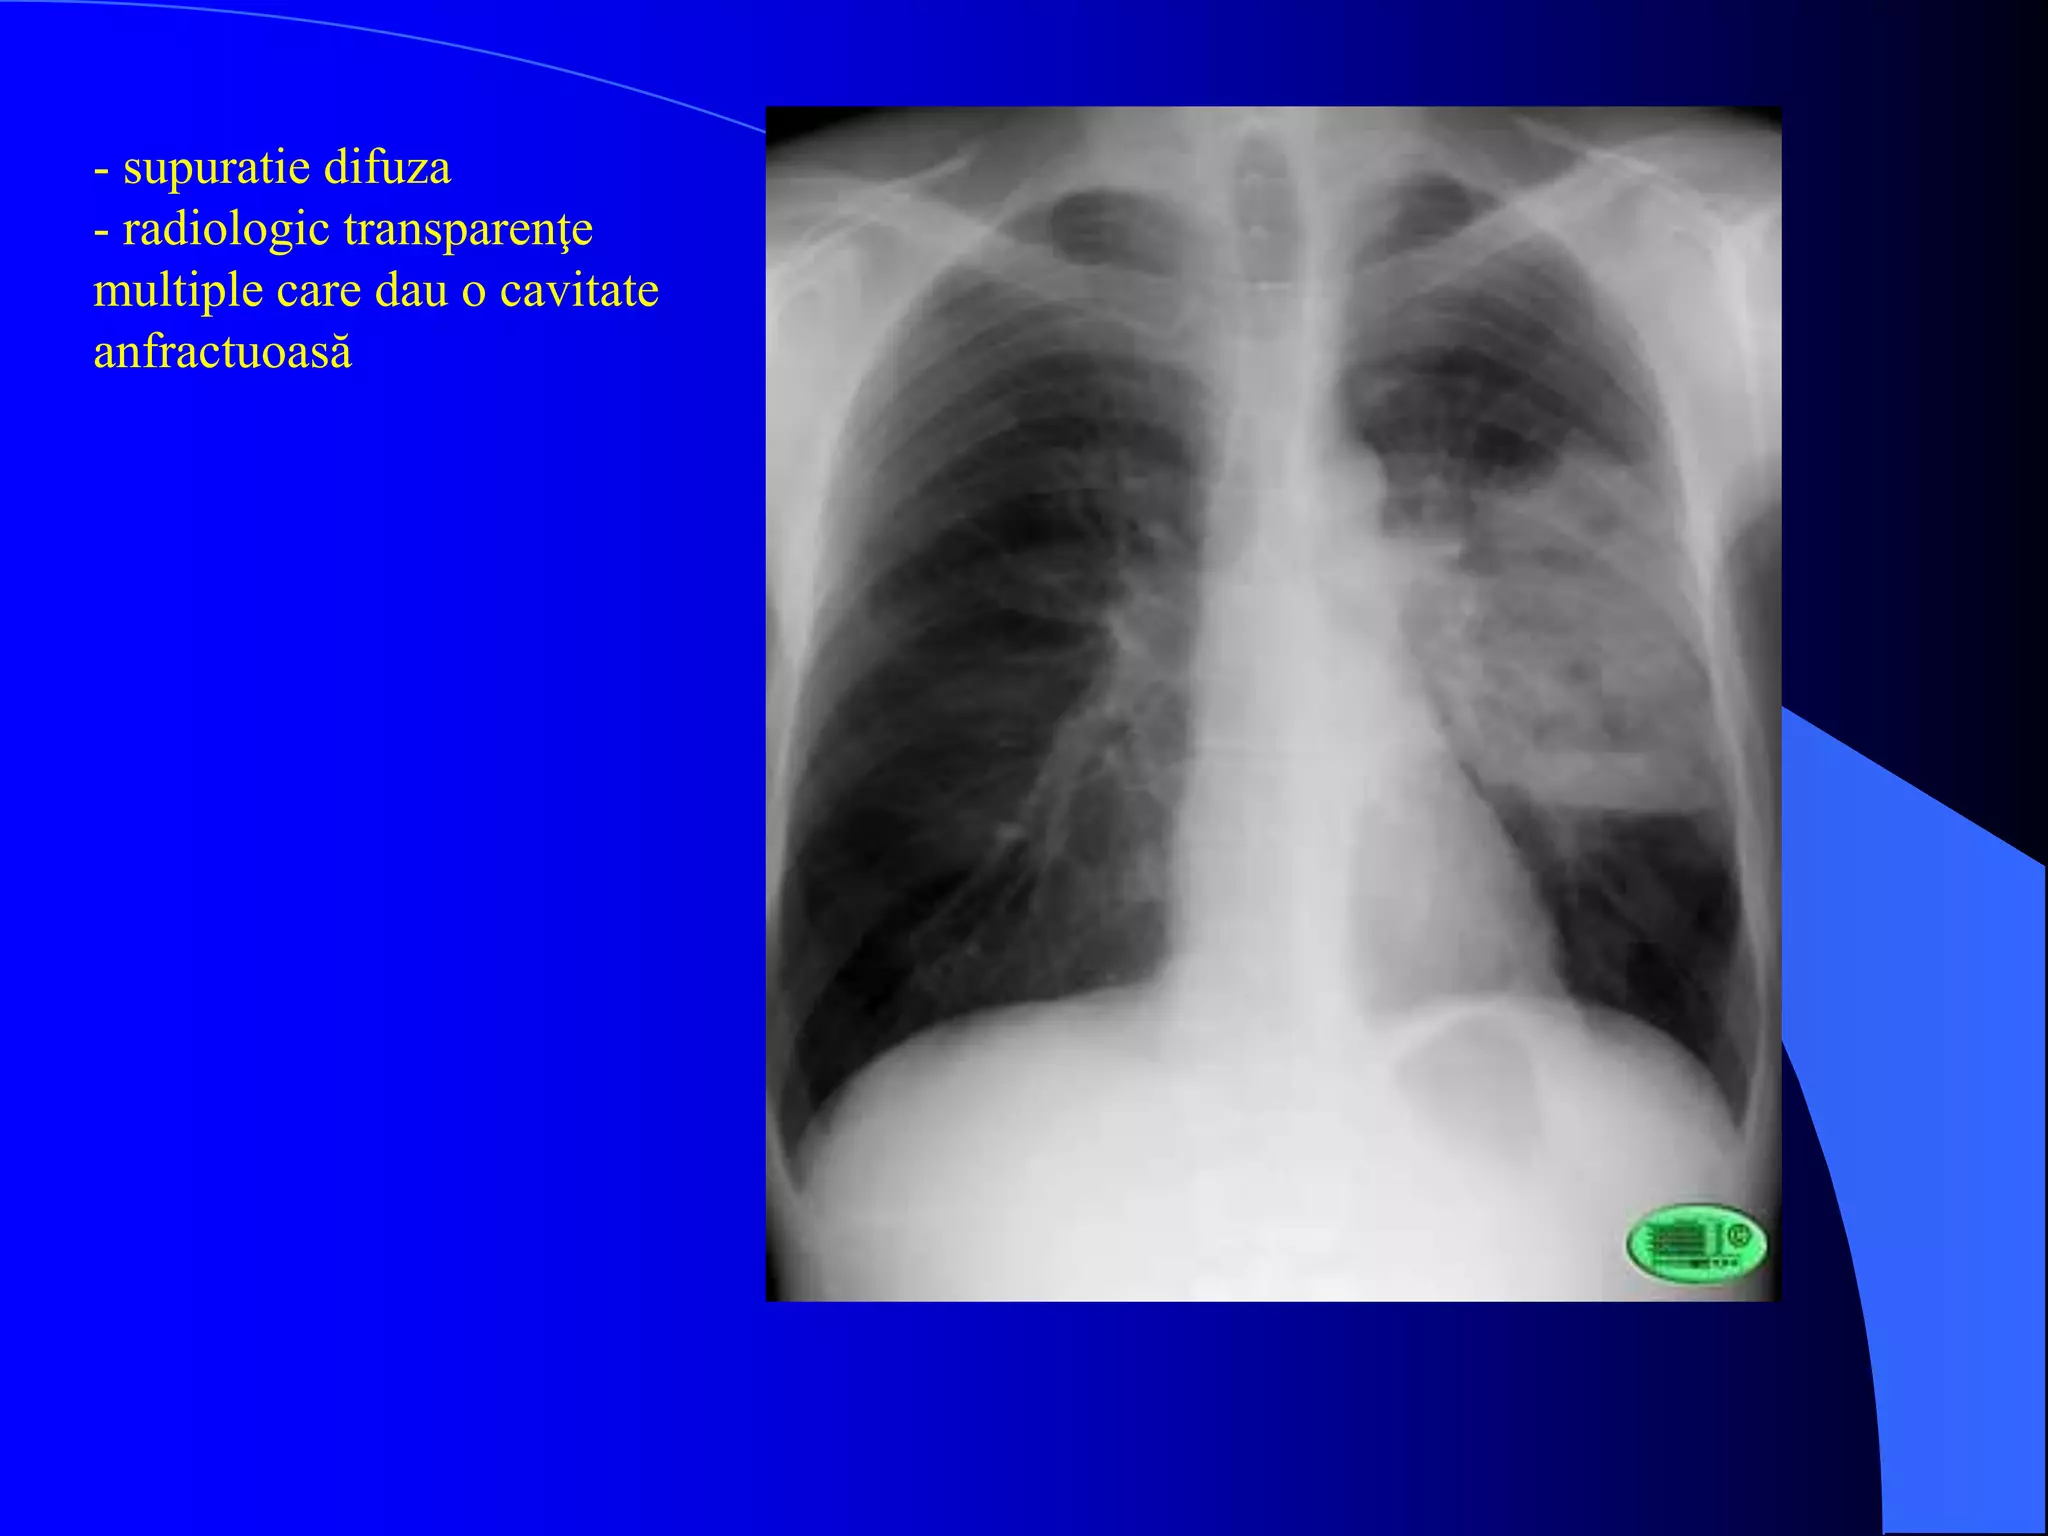

- supuratie difuza

- radiologic transparenţe

multiple care dau o cavitate

anfractuoasă